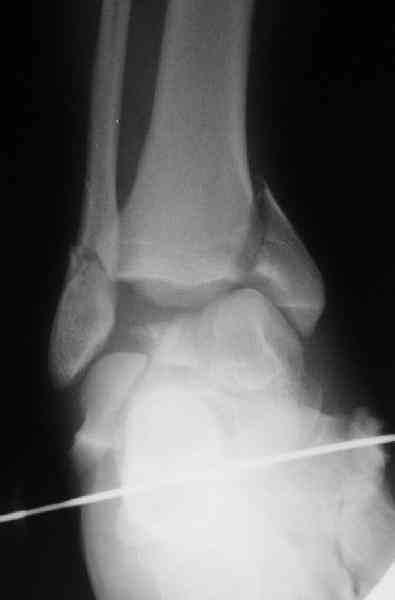

Для оценки состояния нужны дополнительные исследования, например

> Canale или Broden ренгенограммы

повторили рентгенограммы и доделали проекции, к единому мнению все еще не пришли